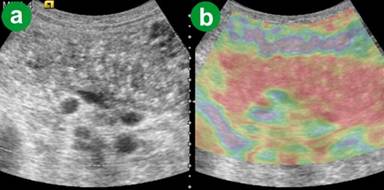

Three of our cases were diagnosed as acute autoimmune pancreatitis: one focal (Figure 7) and two diffused. The eSie touch images were dark black (score 6) and dark red (score 6) on gray and color codes, respectively. Post-steroid therapy scan of a patient six weeks following therapy showed decreased ARFI-VTQ to less than 2 m/s. The eSie touch image (Figure 8) was light gray (score 2) on gray scale and yellowish green (score 2) on color scale.

Figure 7. Focal autoimmune pancreatitis. a. US B-mode image show bulky head of pancreas. b. eSie touch color scale image (dark red area in the head of the pancreas: score 6). |

Figure 8. Focal autoimmune pancreatitis six weeks after steroid therapy. a. US B-mode. b. eSie touch color scale image (yellowish green: score 2). |

As the ARFI-VTQ value expressed by the presently available machine was within the range of 0.50 m/s and 4.95 m/s and not beyond, in cases with ARFI-VTQ values higher than 4.95 m/s, if the eSie touch image was dark black (score 6) on gray scale and patchy red to dark red (scores 5 or 6) on color code (Figure 9), this was considered to indicate hard pancreas (acute inflamed) suggesting acute pancreatitis. In cases of acute resolving pancreatitis, where ARFI-VTQ values were higher than 4.95 m/s but eSie touch image was patchy with bright white (score 1) on gray scale and green/purple (score 1) on color code, it suggested necrotic areas.

Figure 9. Acute-on-chronic calcific pancreatitis. a. US B-mode image. b. eSie touch color scale image (patchy red to dark red: score 5-6). |